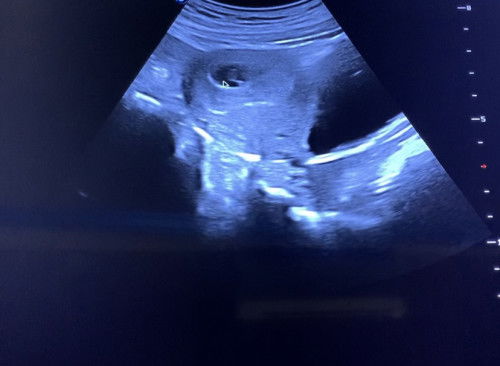

Hai, 3 hari lepas saya pergi scan dr bagitahu kandungan saya dah 10w sbb nampak janin dah besar (tapi saya tak ambil gambar). Semalam saya cuba pergi klinik lain dr bagitahu baru 4w 3d gambar ni gambar scan klinik ni. Saya last period 19/3 and irregular period.